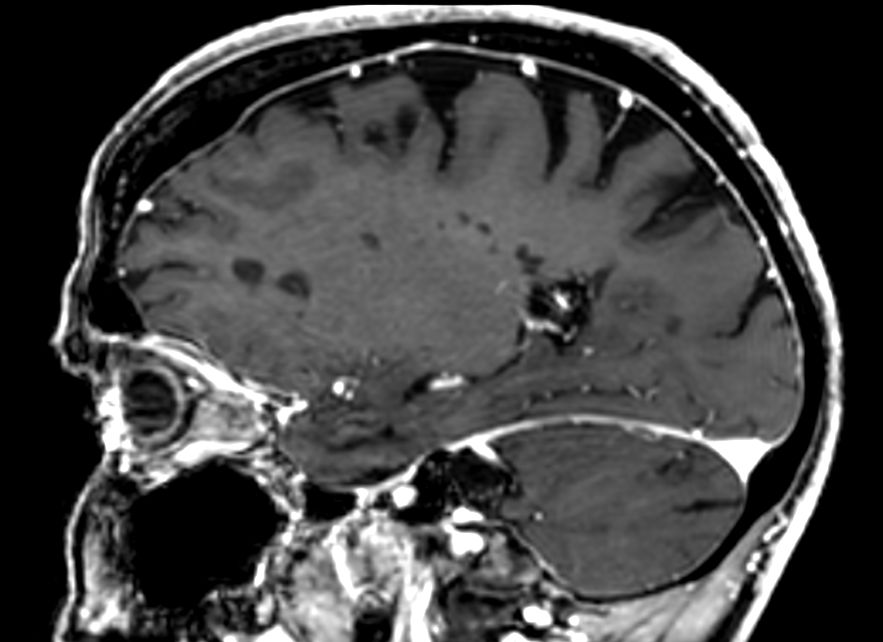

3D T1w FFE +Gado Compressed SENSE

3D T1w FFE (reformat) +Gado Compressed SENSE